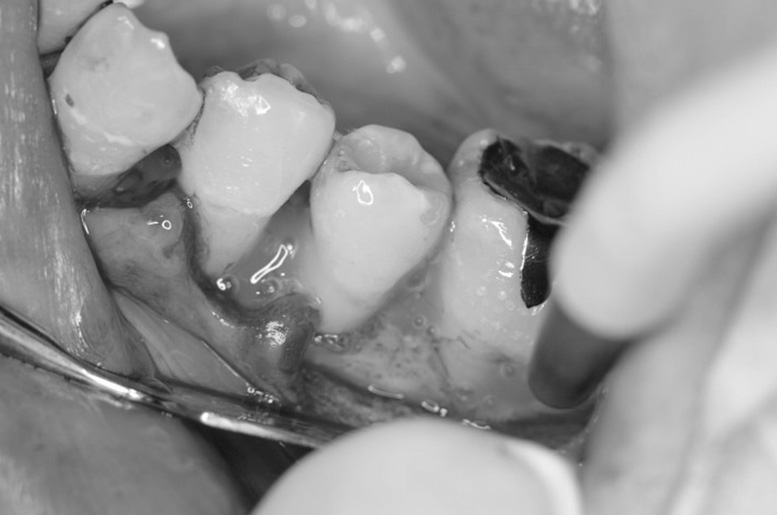

歯周再生療法 精密根管治療 歯周矯正治療 ジルコニアセラミック治療

After

治療期間・回数

約3年・約20回

費用

1,400,000円(歯周矯正治療も含む)